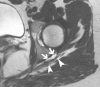

Acetabular paralabral cysts are common. They vary in their clinical presentation and may be asymptomatic or cause pain and restriction at the hip joint. In rare instances they may cause symptoms by compressing local neurovascular structures. We report a case of symptomatic compression of the sciatic nerve by a posteriorly displaced acetabular paralabral cyst.